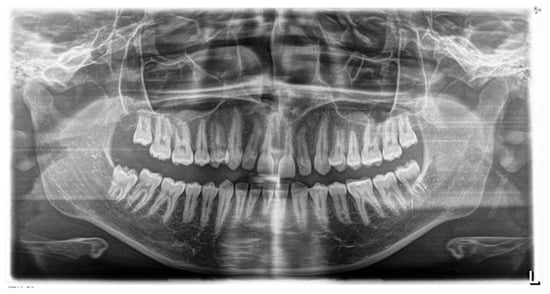

Figure 5. Panoramic radiograph at the end of the treatment. Severe root resorption was observed.

Orthodontic treatment with fixed appliances was continued for another 7 months. After 30 months of orthodontic treatment, the first pantomographic X-ray was taken during orthodontic treatment with fixed appliances. Panoramex showed advanced external resorption of the roots of the upper and lower arch teeth (Figure 5). The X-ray was taken using Orthophos SL 2D (Sirona) with exposure parameters of 69 kV, 12 mA through 14.1 s. The radiation rate was 127. According to this, the decision was made to immediately debond the brackets. After debonding grade 2 mobility of teeth 11 and 21, as part of retention, an upper and lower retention splint was used.